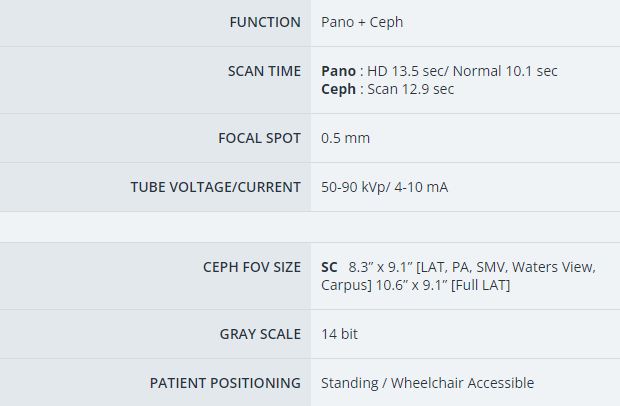

This facory certified Vatech PaX-i SC pan ceph X-ray machine provides consistently clear and detailed panoramic and cephalometric X-ray images, enhancing diagnostic precision and fostering greater treatment acceptance. With dedicated, built-in sensors for both panoramic and cephalometric imaging, this machine ensures exceptional digital imaging quality, while also boosting practice efficiency.